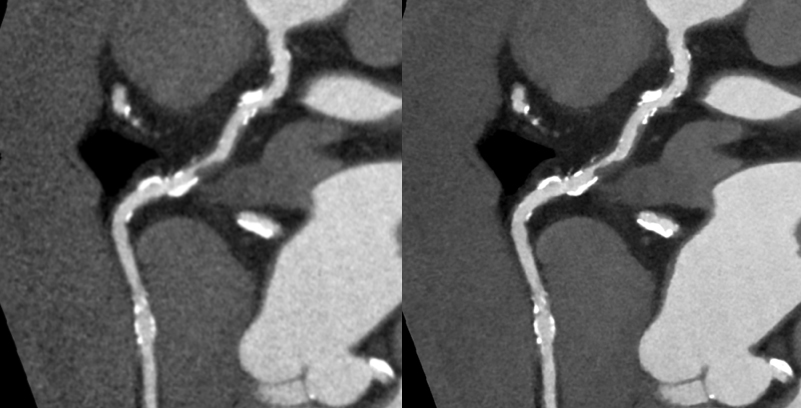

キヤノンメディカルシステムズが開発したPrecise IQ Engine(PIQE)によるディープラーニングの画像によって、冠動脈CT検査で評価が難しい石灰化やステントに接する部分の描出が向上されるため、さらに正確な画像診断が可能となりました。

石灰化症例:左の従来画像と比較して、右の高精細ディープラーニング画像では血管周囲の白い石灰化部分がシャープに描出されています。

ステント症例:左の従来画像と比較して,右の高精細ディープラーニング画像では小さなステントの内部も明瞭に描出されています。

通常の画像(左)に比べ、石灰化(白い部分)を除去した画像(右)では血管狭窄の有無が明瞭に評価できます。

通常の画像(左)ではSTENT内の評価は困難ですが、サブトラクション画像(中央)によって末梢側に高度狭窄を疑われます(矢印)。カテーテル造影(右)でも同様の位置に高度狭窄病変を認めます(矢印)。